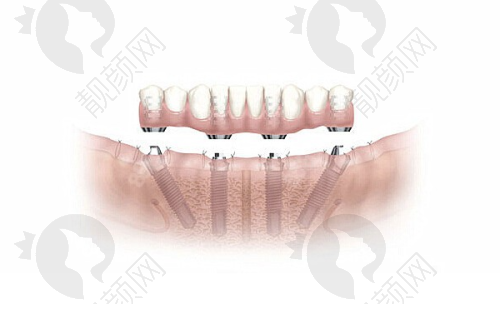

开展的种牙项目丰富,单颗、多颗、半/全口种植牙都能做。单颗种植牙价格4000元起,其中,国产种植牙4000元起,韩系种植牙5000元起,瑞士iti种植牙12500元起,德国贝格种植牙10000元起,美国皓圣种植牙4500元起,瑞典种植牙12000元起。半/全口种植牙价格方面,半/全口韩系种植牙4 - 12万元左右,半/全口瑞士种植牙7 - 25万元左右,半/全口立得用种植牙5 - 20万元左右,半/全口Allon4种植牙4 - 25万元左右。立得用种植牙技术特别有优势,上下颌各仅需4 - 6颗就能修复全口牙,省时省力还省钱。

种牙技术上,衡阳美莱口腔采取数字化种植,比如微创种植牙、all - on - 4种植牙都能做。医院注重种植体与牙冠的美学设计,让种植牙在外观和性能上都接近真牙。种植后还有专人跟踪种植情况,及时处理问题。